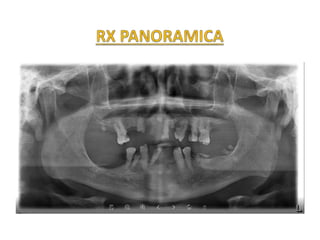

CASO CLÍNICO

HC: 201506674

UNIVERSIDAD PERUANA

CAYETANO HEREDIA

1 2

3

4 5

6

R1 Palomino - 2015